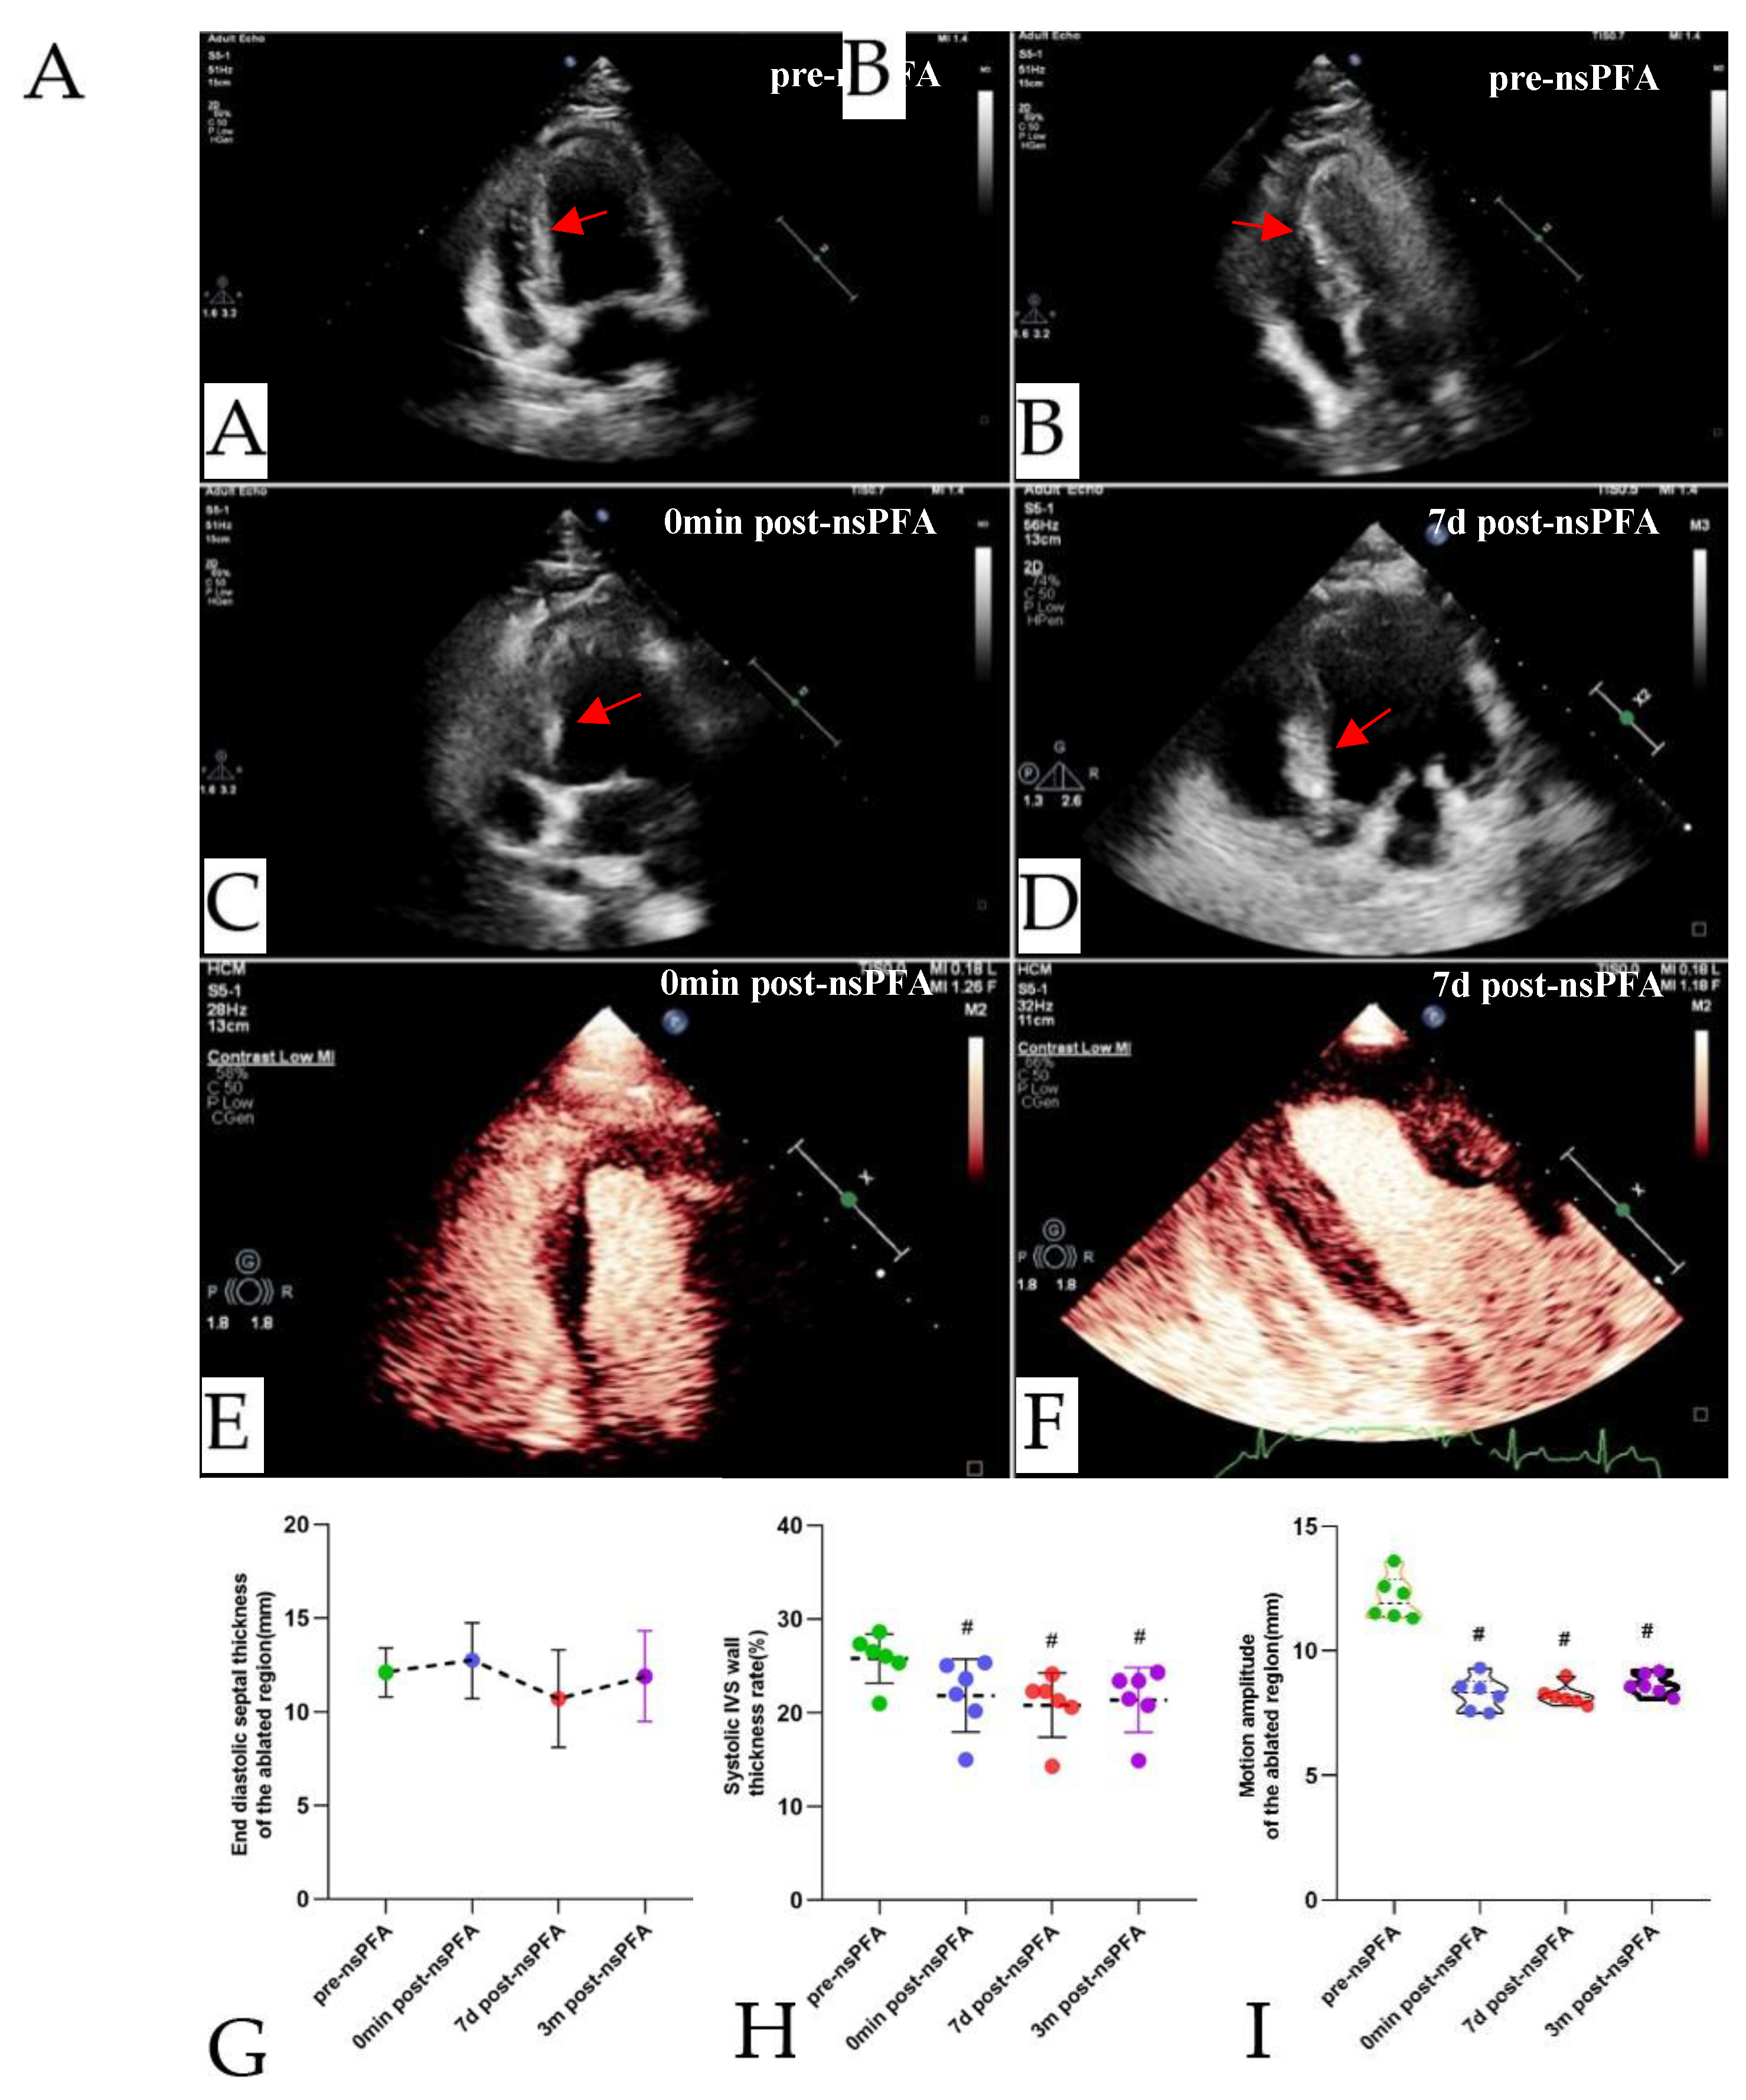

TTE examinations were performed throughout the procedure and at each subsequent follow-up (

Figure 4A and 4B). Subsequent to the ablation procedure, the myocardial area exhibited increased echogenicity on the echocardiographic images that were generated. This change remained after 7 days. By contrast, no significant changes in echo intensity were observed in the non-ablated segments (

Figure 4C and 4D). Postoperative contrast-enhanced echocardiography revealed no significant decrease in myocardial perfusion in the ablated area compared with the non-ablated region (

Figure 4E and 4F). Furthermore, visual assessment of myocardial motion revealed a significant reduction in motion within the ablated region after the procedure, with septal hypokinesis observed after nsPFA. The thickness of the septum in the ablated region did not undergo significant change after nsPFA, immediately following the procedure (F = 1.506,

P = 0.375,

Figure 4G). The rate of systolic wall thickening and motion amplitude decreased significantly immediately following nsPFA, remaining at a lower level (systolic wall thickening rate: F = 15.283,

P = 0.000; motion amplitude: The result of this calculation, F = 21.172,

P = 0.000, is consistent with the findings presented in Fig 4H and4I).

Figure 4.

TTE-guided nsPEF ablation procedure. (A). During preoperative TTE, the apical four-chamber view revealed the left and right ventricles, as well as the IVS. (B). The nsPFA electrode needle punctures the right ventricular apex of the chest wall and enters the basal segment of the IVS (red arrow). (C). Immediately after ablation, the basal IVS exhibited a greater degree of brightness in comparison to the other myocardial segments, as evidenced by TTE image (red arrow). (D). Enhanced echogenicity was still visible in the basal IVS seven days later with no significant changes in other segments (red arrow). Contrast-enhanced echocardiography showed no significant differences in myocardial perfusion between the basal IVS and other segments immediately (E) and seven days (F) following the ablation procedure. The septal thickness (G), systolic wall thickness rate (H), and motion amplitude (I) of the ablation region in the IVS are shown during nsPEF ablation. ( #P < 0.05 vs. pre-nsPFA). nsPEF, nanosecond pulsed electric field; TTE, transthoracic echocardiography; IVS, interventricular septum.